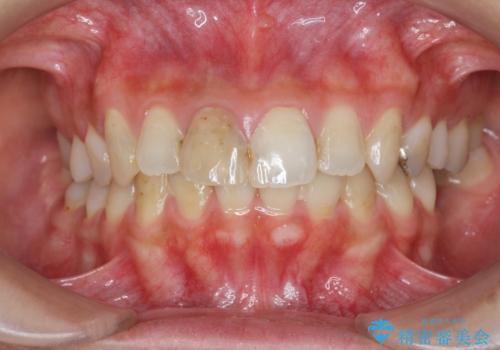

- 「 以前神経を取った歯の変色が気になる。前歯をきれいにして欲しい。」と治療を希望され来院されました。

目立つ上顎前歯に変色・大きな虫歯治療痕が見られ、審美障害を引き起こしています。

虫歯の徹底的な除去、根管治療を行いセラミック治療に入る前の環境をしっかりと整えたのち審美的なジルコニアセラミックで治療を仕上げました。